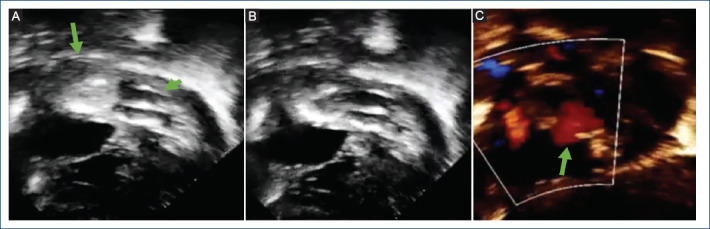

Objectives: Balloon atrial septostomy (BAS) is a palliative procedure mainly for newborns with transposition of the great arteries, currently, this procedure has a class IA recommendation. However, in some cases, this procedure does not achieve an adequate interatrial defect, due mainly to a thickened interatrial septum, this situation led to the development of various techniques to tackle this problem. Therefore, we made a modification to the original technique using two balloons simultaneously instead of one. The objective of this study is to analyze the results of this new modification to the traditional technique (with one balloon) as an alternative for cases with thickened interatrial septum.

Results: Six patients were identified (median age 35 days, median weight 3.4 kg, median size of atrial septal defect before procedure 2.6 mm). All patients underwent to this modification of the BAS with good results and without complications. The modification has some advantages: including to avoid the using of cutting devices or stent placement. In addition, we share the description of this new technique, titled: double "dynamic" BAS.

Conclusion: This brief evidence shown that this modification of de original technique is easy, safe, and cost-effective for cases with a thickened interatrial septum.